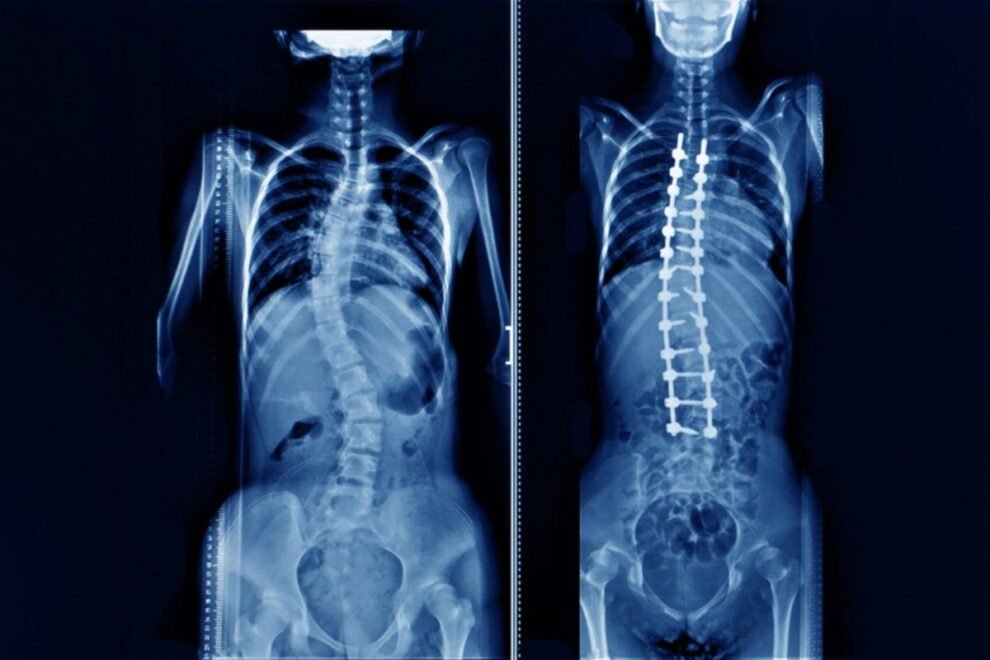

If you have spinal instability or have laminectomies to multiple vertebrae, a fusion may be performed. Fusion is the joining of two vertebrae with a bone graft held together with hardware such as plates, rods, hooks, pedicle screws, or cages. The goal of the bone graft is to join the vertebrae above and below to form one solid piece of bone.There are several ways to create a fusion. The right one for you depends on your own choice and your doctor’s recommendation.

The most common type of fusion is called the posterolateral fusion. The topmost layer of bone on the transverse processes is removed with a drill to create a bed for the bone graft to grow. Bone graft, taken from the top of your hip, is placed along the posterolateral bed. The surgeon may reinforce the fusion with metal rods and screws inserted into the vertebrae. The back muscles are laid over the bone graft to hold it in place.